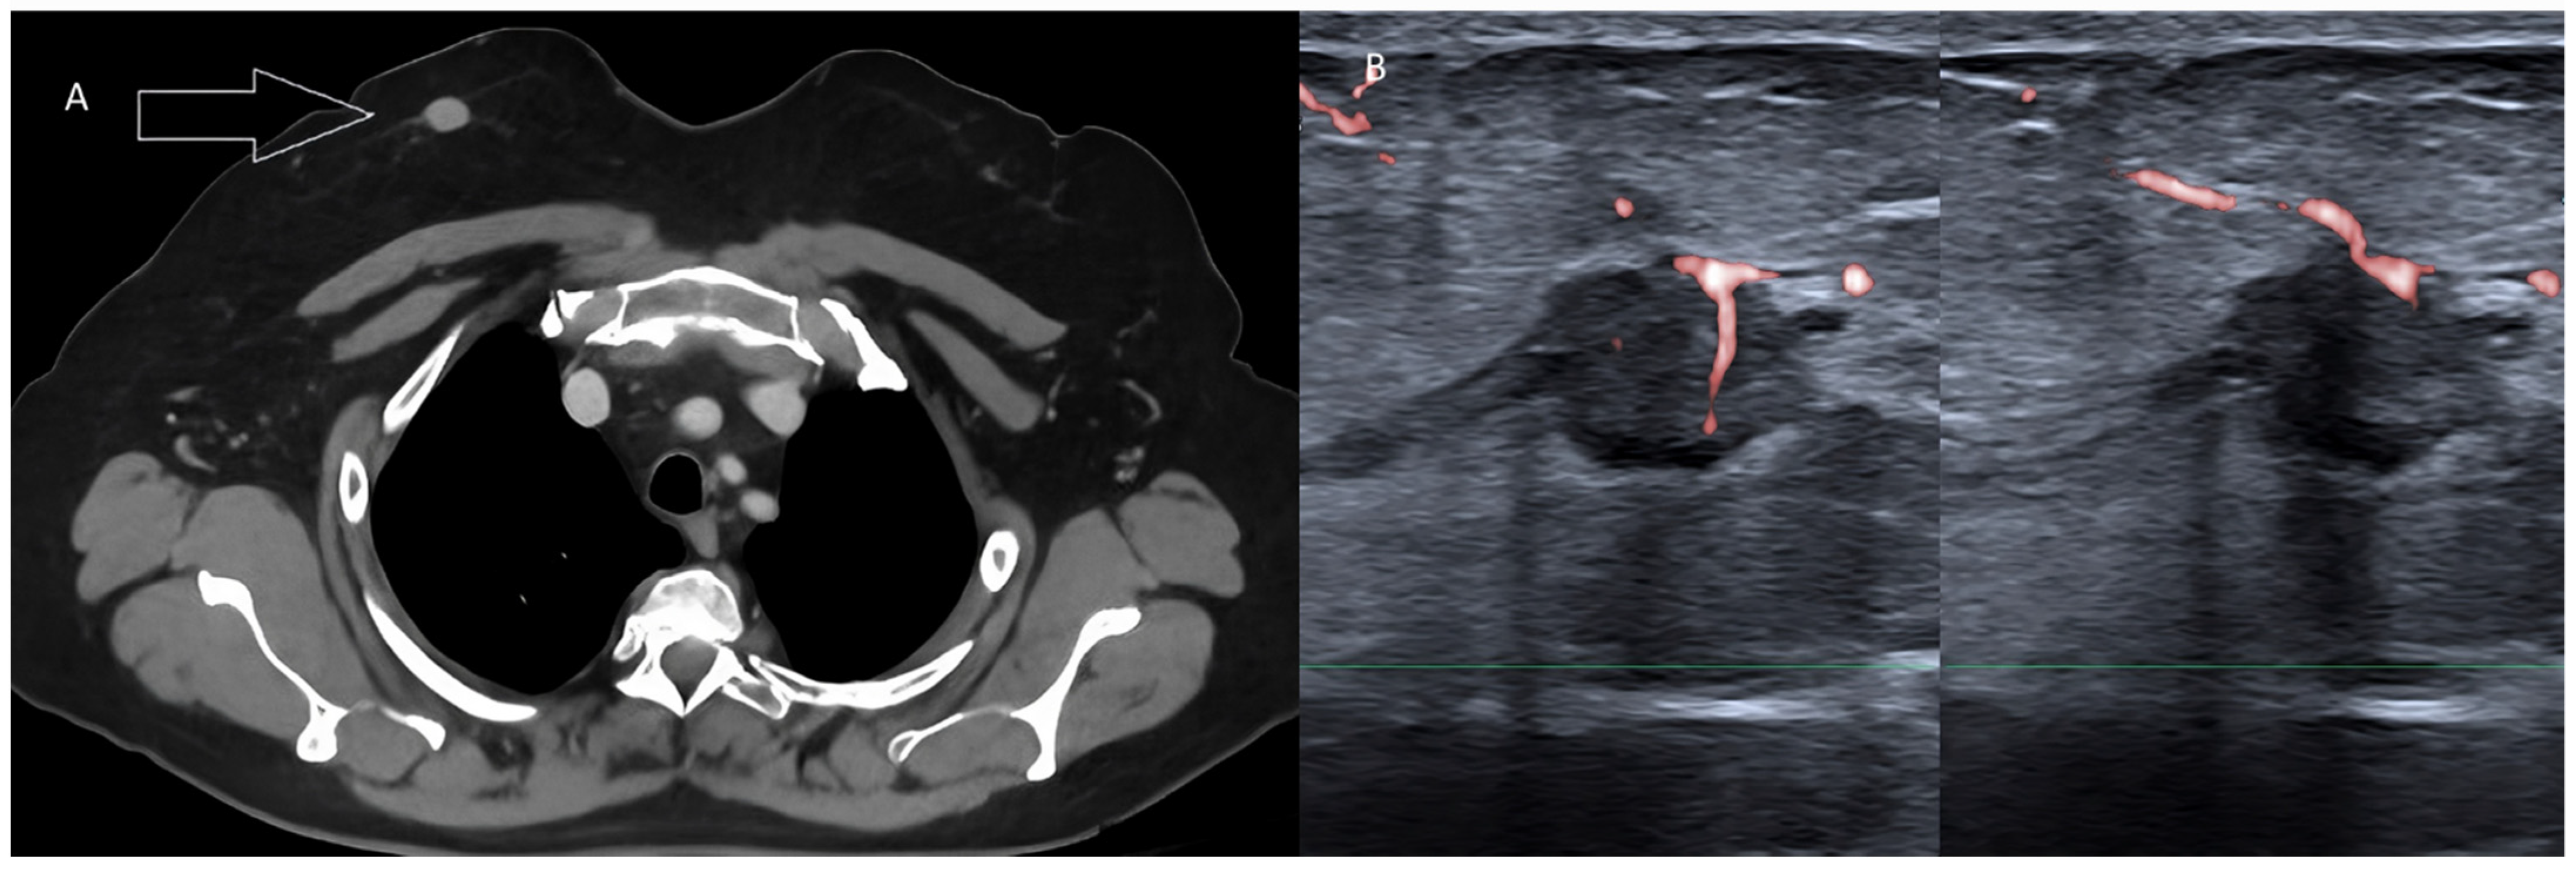

Breast uptakes with a whole-body PET scan can also be further investigated with US to avoid false positive diagnoses. This applies to patients undergoing a PET exam because of breast cancer but also to subjects with non-mammary primary tumors during their staging or follow-up with molecular imaging.

Breast nodules are frequently detected during contrast-enhanced or unenhanced CT exams, chest scans, abdominal scans, or whole-body scans (Figure 11).

US works well as a quick and simple tool to confirm or rule out a nodule and to establish the need for further investigation or for patient follow-up.

Figure 11. Pure tubular carcinoma detected incidentally during whole-body CT in a female patient with rectal cancer. (A) Contrast-enhanced, venous-phase CT scan detecting a nodule within the right breast (arrow). (B) Targeted US scan displaying the malignant lesion.